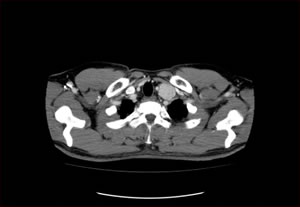

先天性嚢胞のCT画像

先天性嚢胞

良性の嚢胞性疾患であっても、非常に大きかったり、炎症を起こしたりしてしまうと、症状を伴うこともあり、注意が必要です。